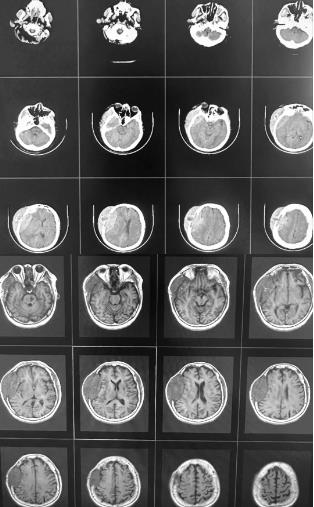

术前头颅CT、MRI图

日前,患者因左侧肢体运动功能障碍并出现喷射性呕吐,被紧急送至交大一附院榆林医院。神经外科王宁教授接诊后,经影像检查发现患者颅骨严重受损,颅内病变紧邻大脑功能区、重要血管及神经。肿瘤直径逾10厘米,深深嵌入头颅,不仅广泛侵蚀颅骨,还向内压迫颅内重要结构,向外突出于头皮。如此巨大且侵袭性强的单一病灶,在临床上极为罕见,对主刀医生的技术水平、临床经验及团队协作能力均构成极大挑战。